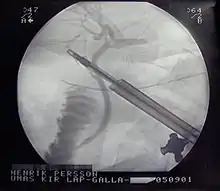

ERCP image showing the biliary tree and the main pancreatic duct. | |

Section across the portal canal of a pig (× 250) An intraoperative cholangiogram, which is an X-ray of bile ducts during a laparoscopic cholecystectomy